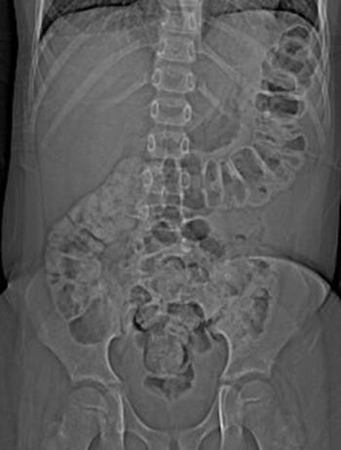

- plain abdominal x-rays:

dilated loops with air-fluid level secondary to ileus; free air is consistent with perforation; in toxic megacolon, the transverse colon is dilated to 6 cm or more in diameter

- abdominal x-ray:

dilated small bowel loops, air-fluid levels throughout abdomen

gaseous distension of large bowel; volvulus suggested by kidney-bean-shape bowel loop